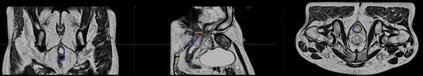

Direct automatic segmentation of objects from 3D medical imaging, such as magnetic resonance (MR) imaging, is challenging as it often involves accurately identifying a number of individual objects with complex geometries within a large volume under investigation. To address these challenges, most deep learning approaches typically enhance their learning capability by substantially increasing the complexity or the number of trainable parameters within their models. Consequently, these models generally require long inference time on standard workstations operating clinical MR systems and are restricted to high-performance computing hardware due to their large memory requirement. Further, to fit 3D dataset through these large models using limited computer memory, trade-off techniques such as patch-wise training are often used which sacrifice the fine-scale geometric information from input images which could be clinically significant for diagnostic purposes. To address these challenges, we present a compact convolutional neural network with a shallow memory footprint to efficiently reduce the number of model parameters required for state-of-art performance. This is critical for practical employment as most clinical environments only have low-end hardware with limited computing power and memory. The proposed network can maintain data integrity by directly processing large full-size 3D input volumes with no patches required and significantly reduces the computational time required for both training and inference. We also propose a novel loss function with extra shape constraint to improve the accuracy for imbalanced classes in 3D MR images.

翻译:3D医学成像的物体,如磁共振成像(MR)成像的直接自动分离,具有挑战性,因为往往需要精确地确定大量调查中大量存在复杂地理不对称的单个物体。为了应对这些挑战,大多数深层学习方法通常会大大提高其模型内可训练参数的复杂性或数量,从而提高其学习能力。因此,这些模型一般需要在运行临床MR系统的标准工作站上花很长的推断时间,并限于高性能的计算机硬件,因为它们的记忆要求很大。此外,要在这些大型模型中安装3D数据集,还要利用有限的计算机记忆,经常使用交换技术,例如补对称培训等,以牺牲从对诊断目的具有临床重要性的投入图像中获得的精细比例的几何地理信息。为了应对这些挑战,我们提出一个具有浅度记忆足迹的银色网络,以有效减少为状态性能所需的模型参数数量。这对于实际就业至关重要,因为大多数临床环境只有低端硬件,计算机功能和记忆有限。拟议的网络可以通过直接处理全尺寸三维化技术来保持数据的完整性,直接处理全尺寸的全尺寸三维的图像,从而大幅改进所需的超度变压的磁度计算。